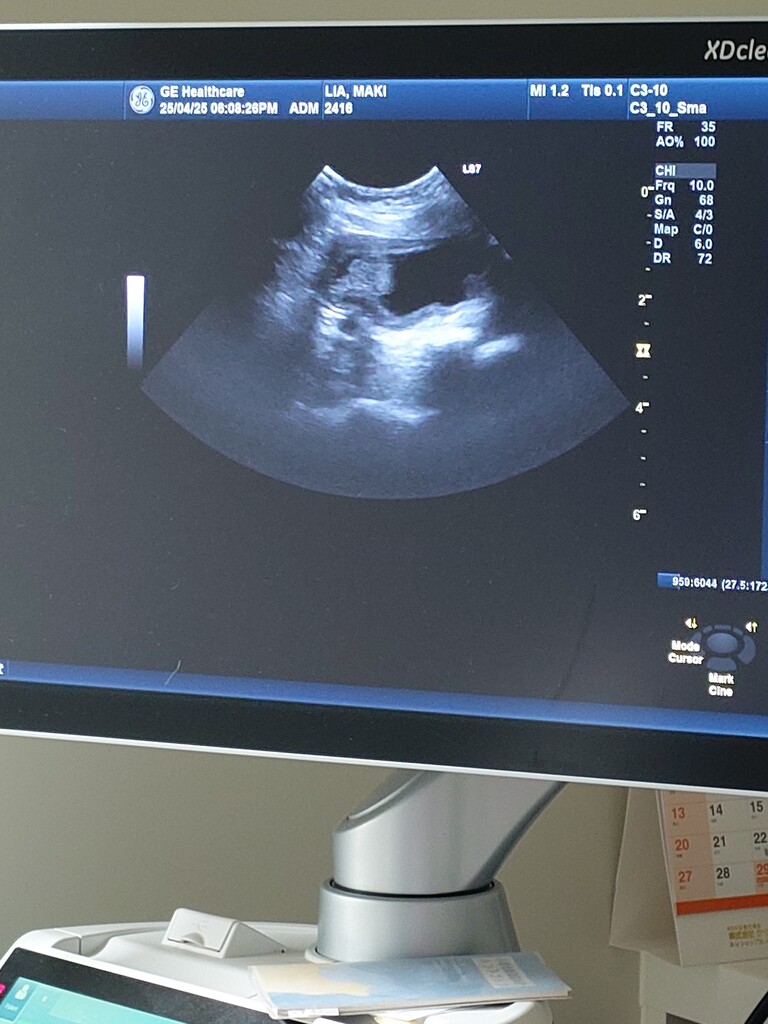

癌や皮膚炎で薬を飲んでいる事もあり

3日程服用を止めて見て

20日に院長先生の再診予定です。